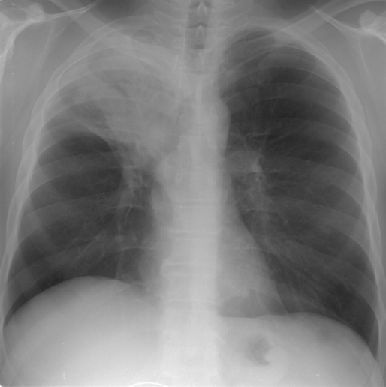

III степень ;нарушения бронхиальной проходимости характеризуется следующими рентгенологическими данными: легочная ткань в состоянии ателектаза треугольной формы, зона ателектаза соответствует сегменту (или доле, или легкому) в зависимости от калибра пораженного бронха (рис. 1). Объем легочной ткани резко уменьшен, вследствие чего отмечается смещение междолевых щелей и сосудистых стволов в соседних отделах. Присоединение пневмонии, распада легочной ткани или опухоли, наличия метастазов в регионарных лимфатических узлах или их гиперплазия, метастатический или воспалительный плеврит дополняют рентгенологическую картину неоднородным затемнением легочной ткани в проекции пораженного сегмента или доли, ячеистыми просветлениями, расширением корня и полицикличностью его контуров, наличием жидкости в плевральной полости. Тень первичной опухоли может выявиться при обзорной рентгенографии. При томографическом исследовании просвета бронха определяется картина “культи” или “ампутации” бронха, возможна также оценка легочной ткани в спавшейся доле или сегменте.

Рисунок 1. Центральный рак верхней доли правого легкого с ателектазом доли